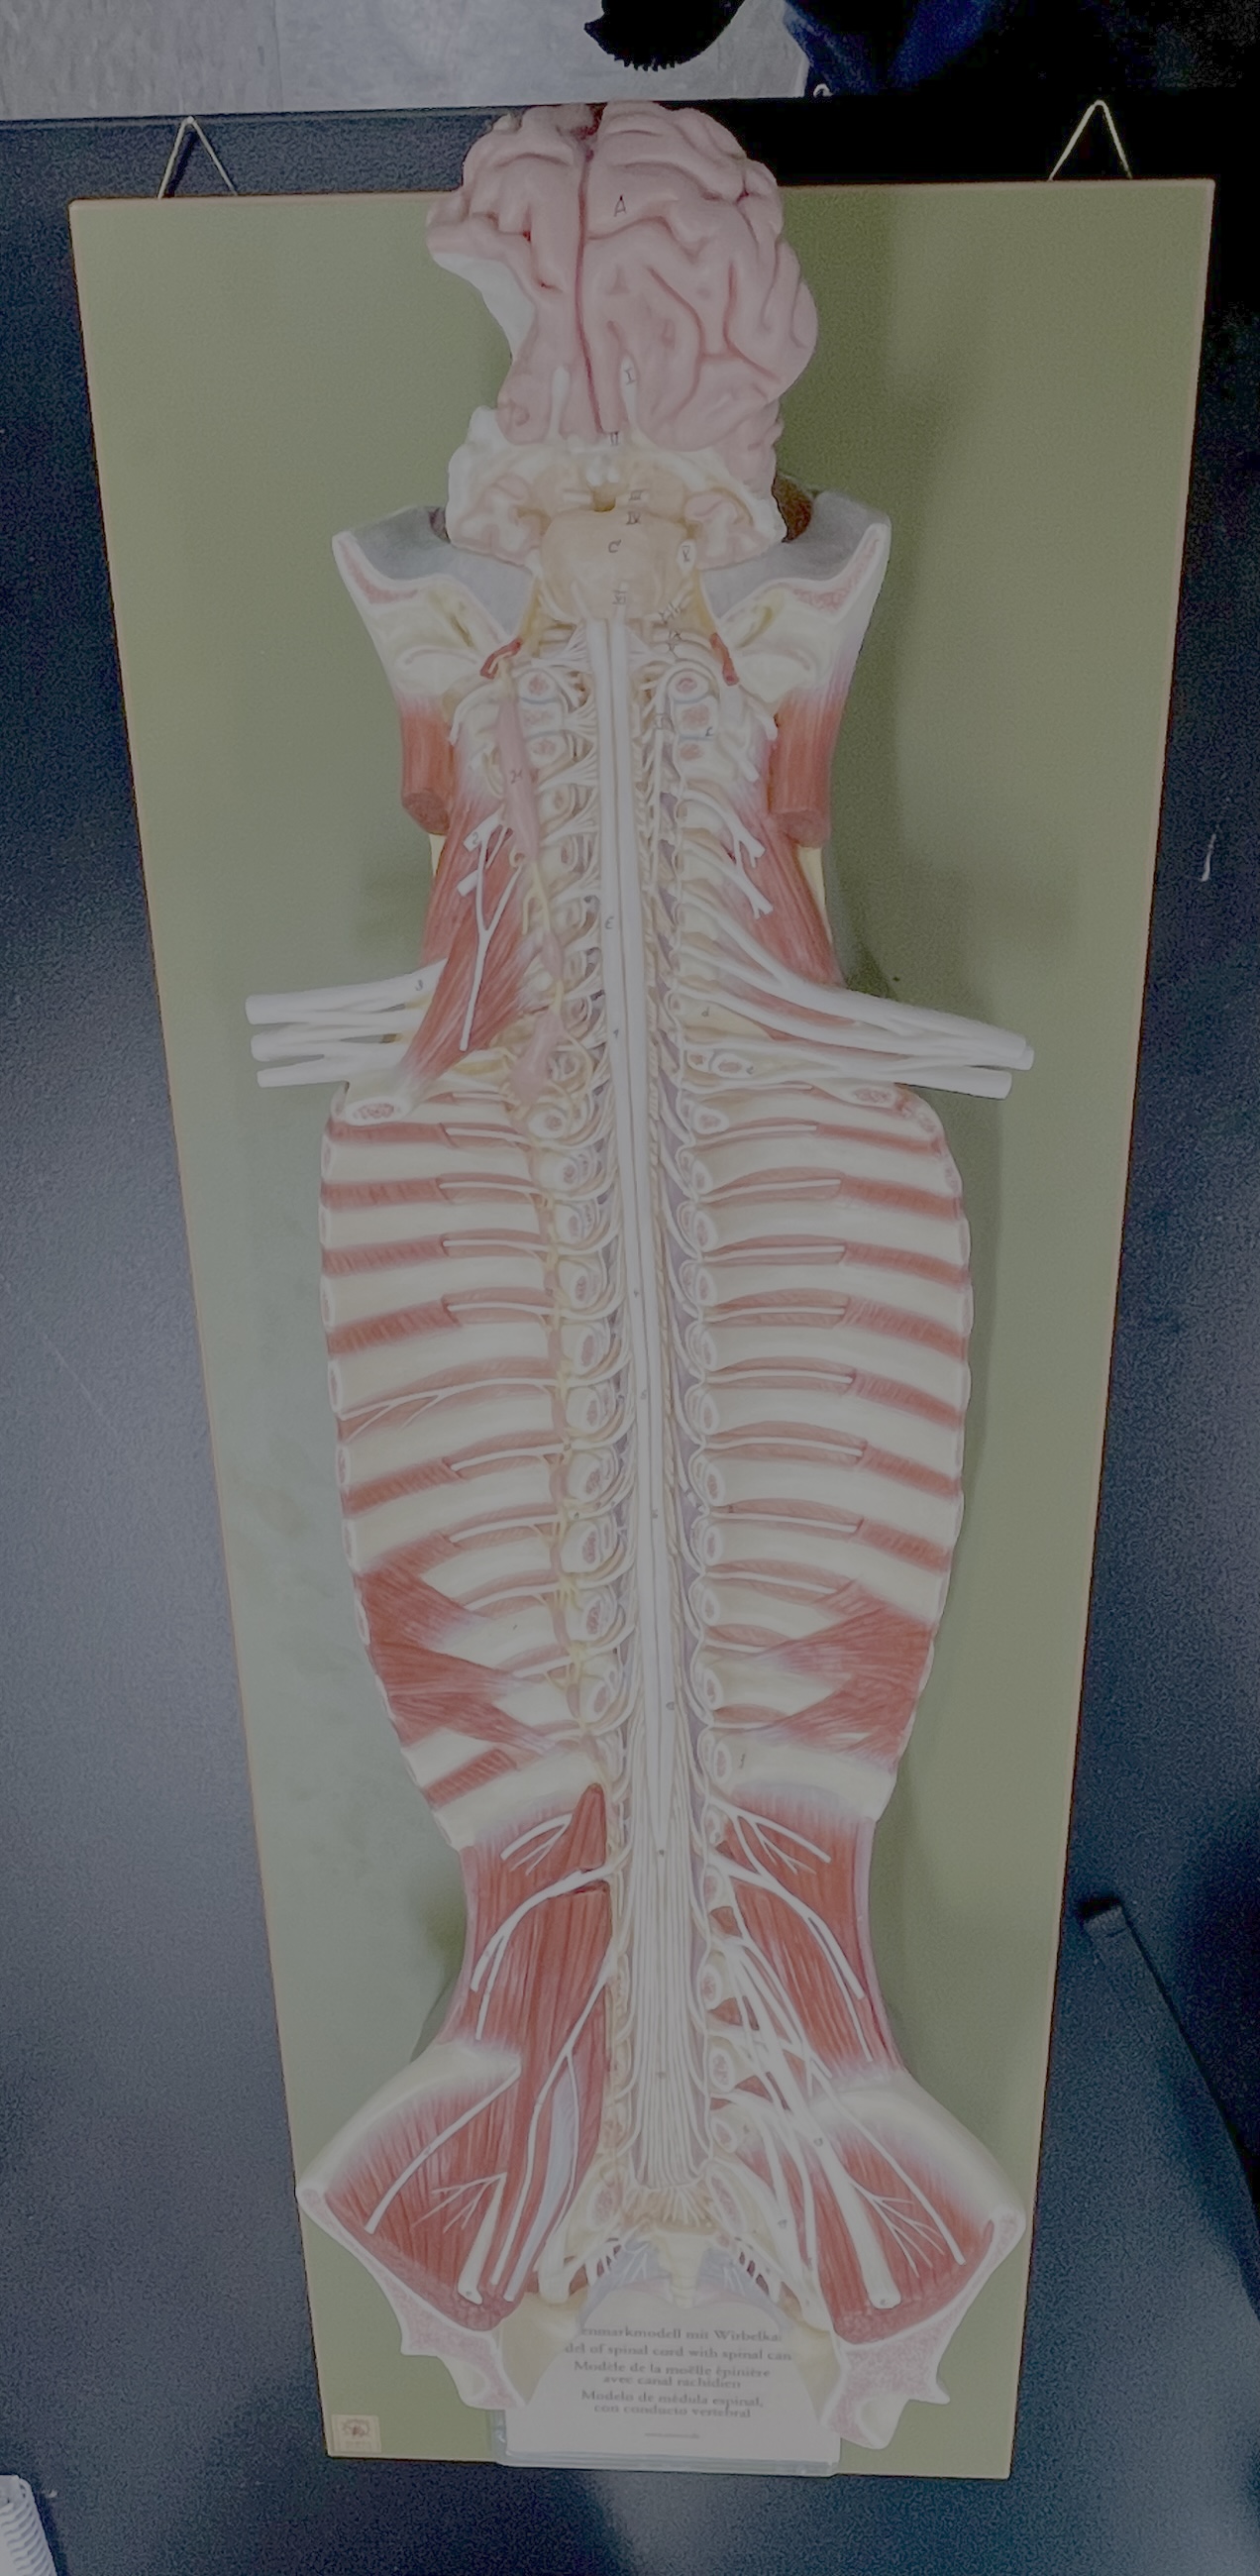

What type of spinal nerve is this? How many pairs?

cervical (8 pairs)

What type of spinal nerve is this? How many pairs?

thoracic (12 pairs)

What type of spinal nerve is this? How many pairs?

lumbar (5 pairs)

What type of spinal nerve is this? How many pairs?

sacral (5 pairs)

What type of spinal nerve is this? How many pairs? (not pictured)

coccygeal (1 pair)

cervical enlargement

cervical enlargement

thoracic segment

lumbar enlargement

lumbar enlargement

conus medullaris

conus medullaris

filum terminale

cauda equina

sympathetic chain ganglia

cervical plexus – phrenic nerve

cervical plexus – phrenic nerve

brachial plexus – ulnar nerve

brachial plexus – median nerve

brachial plexus – radial nerve

lumbar plexus – femoral nerve

lumbar plexus - femoral nerve

sacral plexus – sciatic nerve

sacral plexus – sciatic nerve